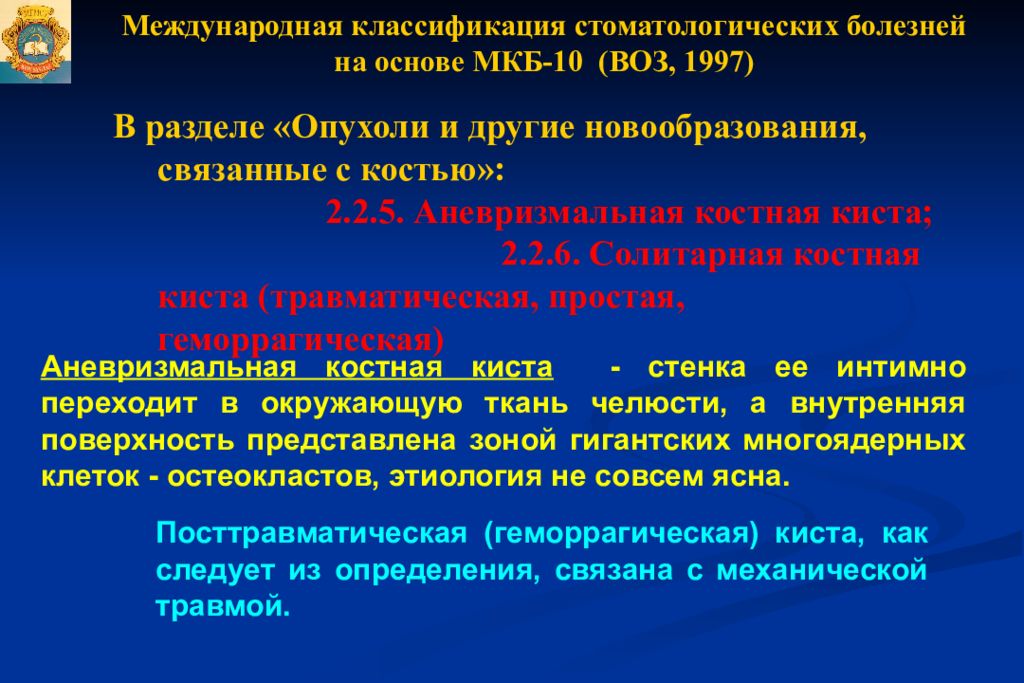

Код мкб 10 атерома головы

Код мкб 10 атерома головы 109 фото